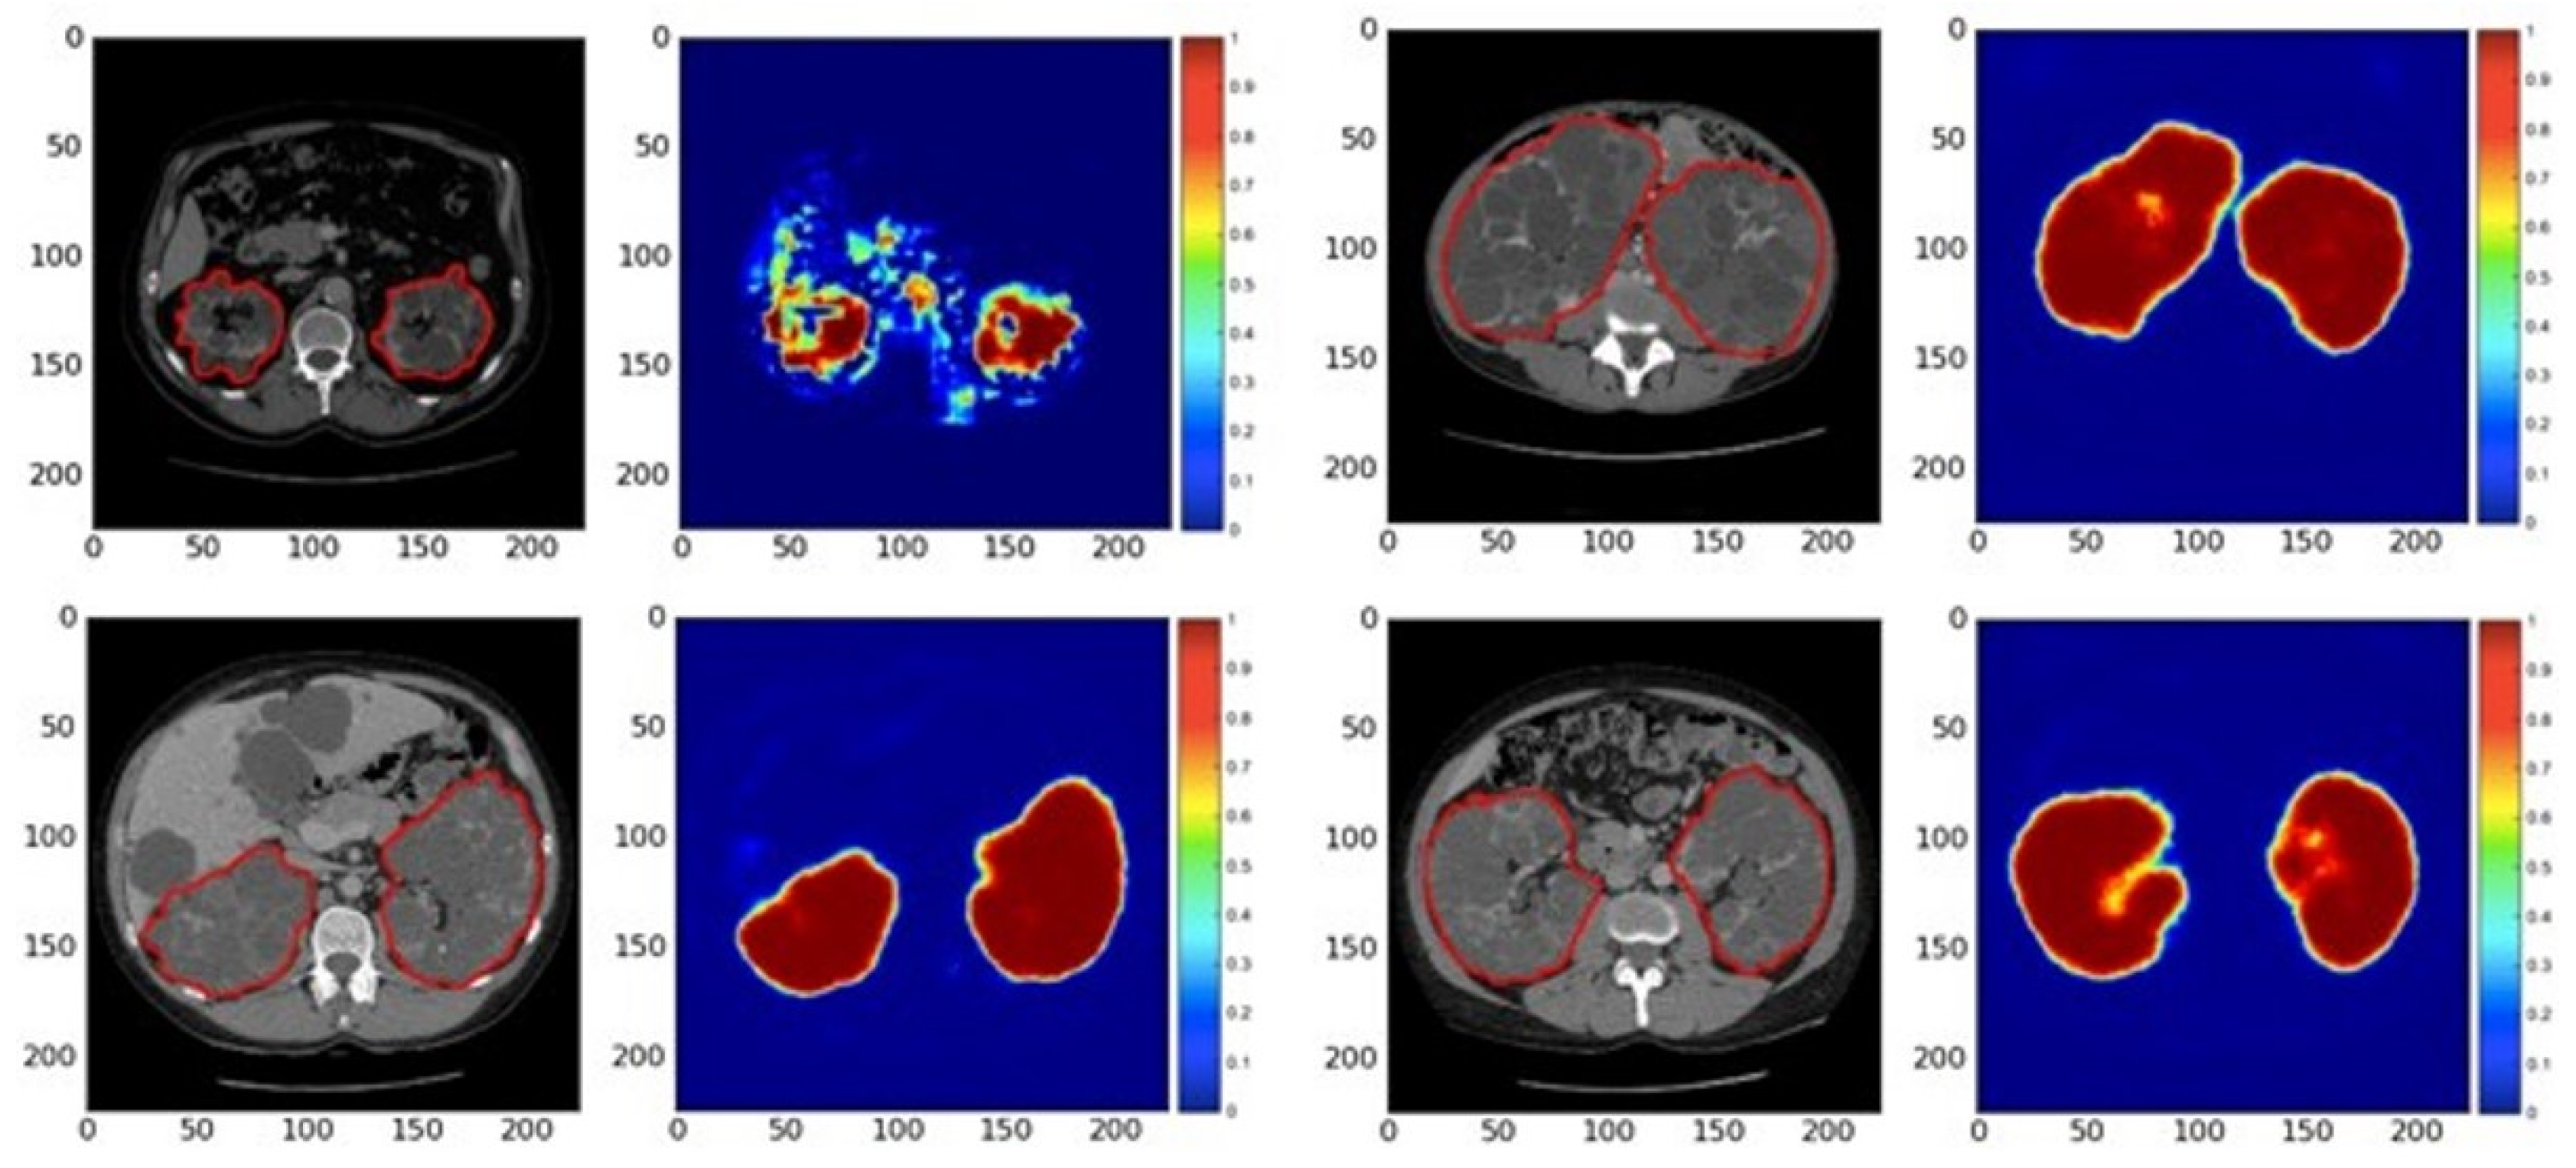

3.3. Deep Learning Methodologies in Diagnosing Chronic Kidney Diseases

- Sharma, K.; Rupprecht, C.; Caroli, A.; Aparicio, M.C.; Remuzzi, A.; Baust, M.; Navab, N. Automatic Segmentation of Kidneys using Deep Learning for Total Kidney Volume Quantification in Autosomal Dominant Polycystic Kidney Disease. Sci. Rep. 2017, 7, 2049. [Google Scholar] [CrossRef] [PubMed]